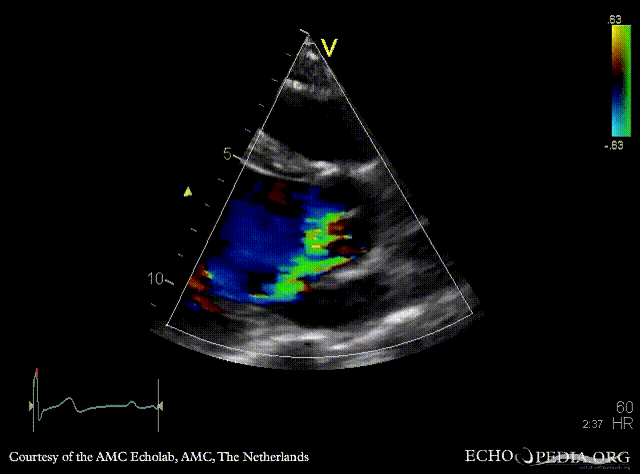

E00231.gif E00232.gif

PLAX: prolapse of aortic valve PLAX: Color Doppler severe aortic regurgitation, eccentric jet